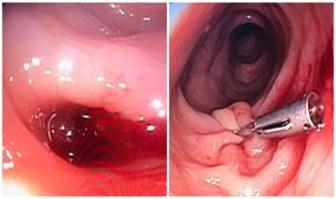

CRITERIOS MAYORES

Hemocultivos positivos (95% de casos) para microorganismos típicos:

Estreptococos, Estafilococo y Enterococo

En caso de Coxiella Burnetii serología: IgG anticuerpo > 1:8000 Ecocardiografía positiva (80 % de casos)

2 (ENAM 2011) (ENARM 2015) (ENAM EXTRA 2020) (ENAM EXTRA 2023) 1

Masa oscilante sugerente de verruga o absceso o dehiscencia de prótesis.

Nueva regurgitación valvular (el aumento o cambio en el soplo preexistente)

(ENAM 2011) 3 (ESSALUD 2012) (ENARM 2016) (ENARM 2015)

Lesión predisponente o ADVP

Fiebre > 38°

Fenómenos embólicos: aneurismas micóticos (10 %), hemorragias conjuntivales, hemorragias “en astilla” en el lecho subungueal las lesiones de Janeway (indoloras, rojizas, en palmas y plantas).

Fenómenos inmunológicos: factor reumatoide positivo, nódulos de Osler (dolorosos, aparecen en los pulpejos y las manchas de Roth en el fondo de ojo).

Hemocultivos positivos que no alcanzan el criterio mayor.

El diagnóstico definitivo de endocarditis infecciosa se establece en presencia de cualquiera de los siguientes:

Criterios patológicos

Lesiones patológicas: como vegetación o absceso intracardiaco que demuestran endocarditis activa en la histología. Microorganismos: demostrados por cultivo o histología de una vegetación o un absceso intracardiaco.

Criterios clínicos

2 mayores, un mayor y 3 menores o 5 menores.